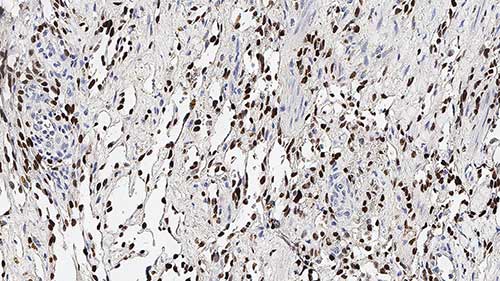

Human skin, Kaposi's sarcoma: immunohistochemical staining for HHV8. Note nuclear staining of neoplastic spindle cells. Human Herpesvirus 8: clone 13B10

Human herpesvirus type 8 (HHV8), is the proposed etiological agent of Kaposi's sarcoma (KS). It is reported that HHV8 has been demonstrated in KS tissues by immunohistochemistry, in situ PCR and also in situ hybridization. HHV8 encodes a latent nuclear antigen (LNA) which is the product of the viral gene ORF73. LNA is capable of forming a complex with retinoblastoma susceptibility gene product which may be related to its oncogenic activity. HHV8 has been reported to be expressed in multicentric Castleman's disease (MCD) and in angioimmunoblastic lymphadenopathies. The localization of HHV8 in subcapsular spindle cell proliferations, which is where early intranodal KS begins, and endothelial cells in Castleman's disease may explain the link between intranodal KS and MCD. In MCD, HHV8 is reported to be expressed in mantle zone large immunoblastic B cells.